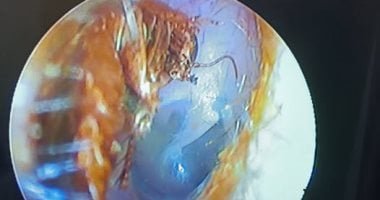

وأكد الأطباء أن الشاب حضر إلى المستشفى وهو يعاني من آلام شديدة في الأذن وصعوبة في السمع، وبعد الفحص تبين وجود جسم غريب تحرك داخل الأذن.

وبعد إجراء عملية دقيقة، تمكن الفريق الطبي من استخراج الصرصور الذي تسبب في الالتهاب والألم الحاد، وتمت العملية بنجاح وسط متابعة دقيقة لحالة المريض.